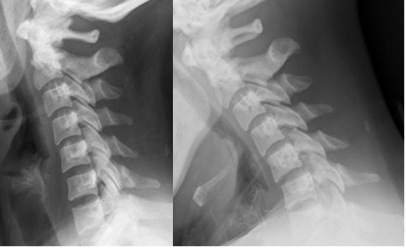

Las proyecciones dinámicas en flexión y extensión se utilizan ante la sospecha de lesión ligamentaria. (38). Pueden dar falsos negativos y se usan para confirmar, pero no descartan lesiones. (38).

En la fase aguda son difíciles de realizar por el dolor y espasmo muscular y están contraindicadas en pacientes inconcientes y neurológicamente intactos. (7, 38, 40). En la mayoría de los casos no muestran alteraciones adicionales y las realizadas después de 2 semanas, tienen mas sensibilidad para detectar la inestabilidad. (7, 10). (Fig 168 a 172).

A nivel cervical se puede tolerar hasta 2 mm de desalineación en las líneas posteriores y el espacio intervertebral posterior, no debe ser mas ancho que el anterior. (38). (Fig 169).